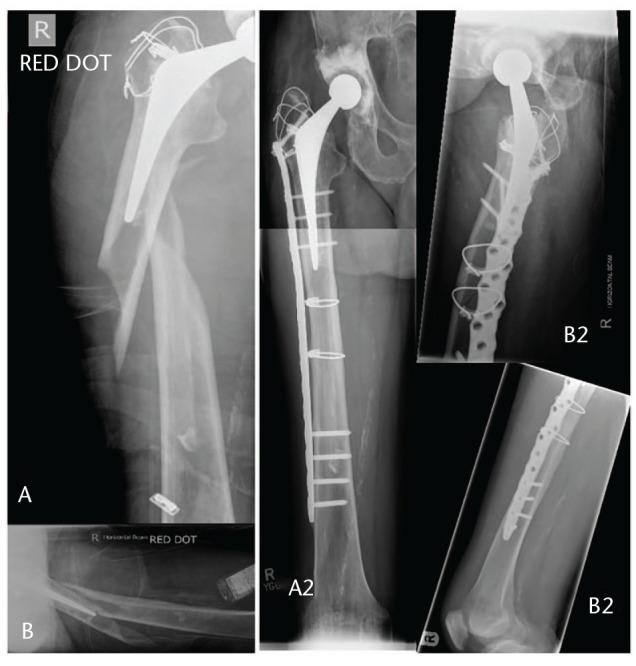

The Vancouver classification is still a useful tool of communication and stratification of periprosthetic fractures, but besides the three parameters it considers, clinicians should also assess additional factors.Combined advanced trauma and arthroplasty skills must be available in departments managing these complex injuries.Preoperative confirmation of the THA (total hip arthroplasty) stability is sometimes challenging. The most reliable method remains intraoperative assessment during surgical exploration of the hip joint.Certain B1 fractures will benefit from revision surgery, whilst some B2 fractures can be effectively managed with osteosynthesis, especially in frail patients.Less invasive osteosynthesis, balanced plate-bone constructs, composite implant solutions, together with an appropriate reduction of the limb axis, rotation and length are critical for a successful fixation and uneventful fracture healing. Cite this article: 2021;6:75-92. DOI: 10.1302/2058-5241.6.200050.

温哥华分类仍然是假体周围骨折沟通和分层的有用工具,但除了它所考虑的三个参数外,临床医生还应评估其他因素。处理这些复杂损伤的科室必须具备综合的高级创伤和关节置换技术。全髋关节置换术(THA)术前稳定性的确认有时具有挑战性。最可靠的方法仍然是在髋关节手术探查期间进行术中评估。某些B1型骨折将受益于翻修手术,而一些B2型骨折可以通过接骨术有效处理,尤其是在体弱患者中。微创接骨术、平衡的钢板-骨结构、复合植入物解决方案,以及适当矫正肢体轴线、旋转和长度,对于成功固定和骨折顺利愈合至关重要。引用本文:2021;6:75-92。DOI:10.1302/2058-5241.6.200050。